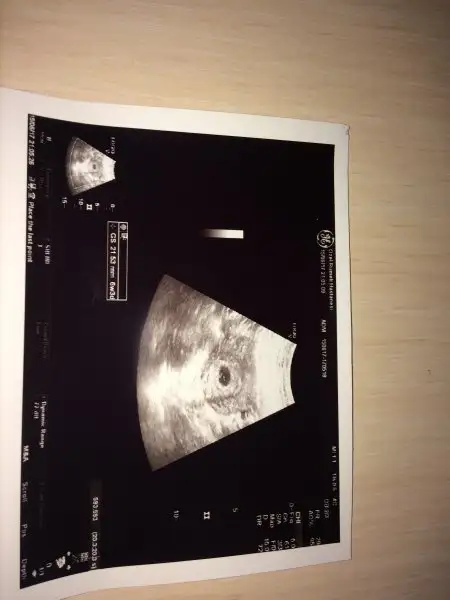

kızlar gitti karın ultrasonuyla 6 hafta 3 günlügüz doktor son adet tarihinle uyumlu olsa 4.5 haftalık olurdu dedi sen erken yumurtlamışsın dedi haftaya kalp atışı için gidicem bebek net görünmedi kordonu göründü :)

• IMG_1868.webp

11,8 KB · Görüntüleme: 74

Vajinal baksa görünürmüş canım, benim doktorum şu an sadece vajinal bakıyor. Neyse sonuçta geçen haftaya göre gelişmiş, önemli olan da bu.

Bende ögle düşündüm vjinal baktırsaydım keşke dedim neyse çarşamba akşamı hem bebegi hem kalbini net duyarım kızımda 6+6 da kalbini duymuştuk.

Cok şükür gelişiyor önemli olan bu dedigin gibi